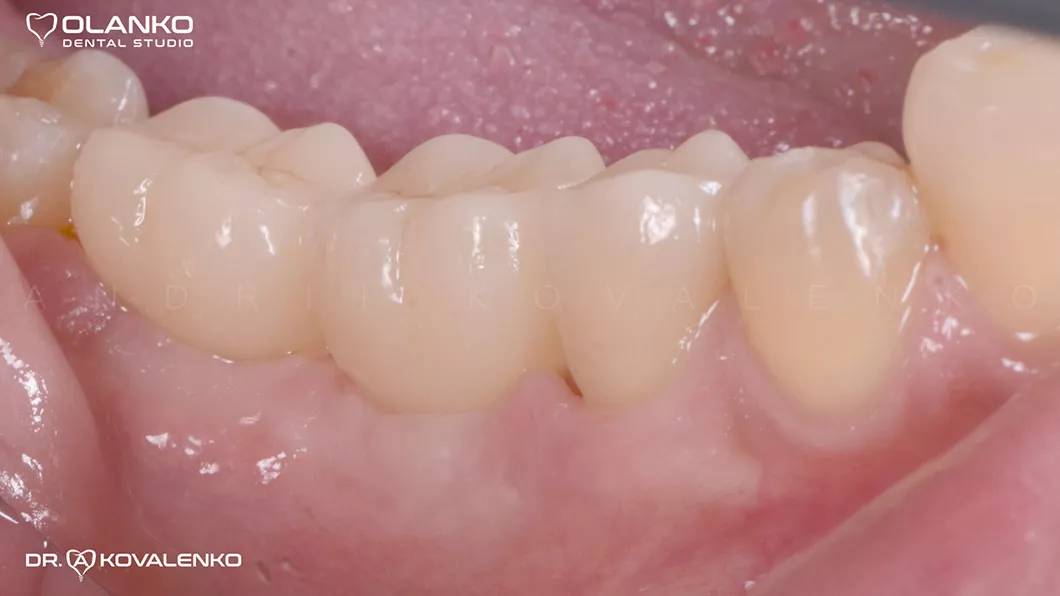

Готовые цельнокерамические коронки

Вид после фиксации коронок